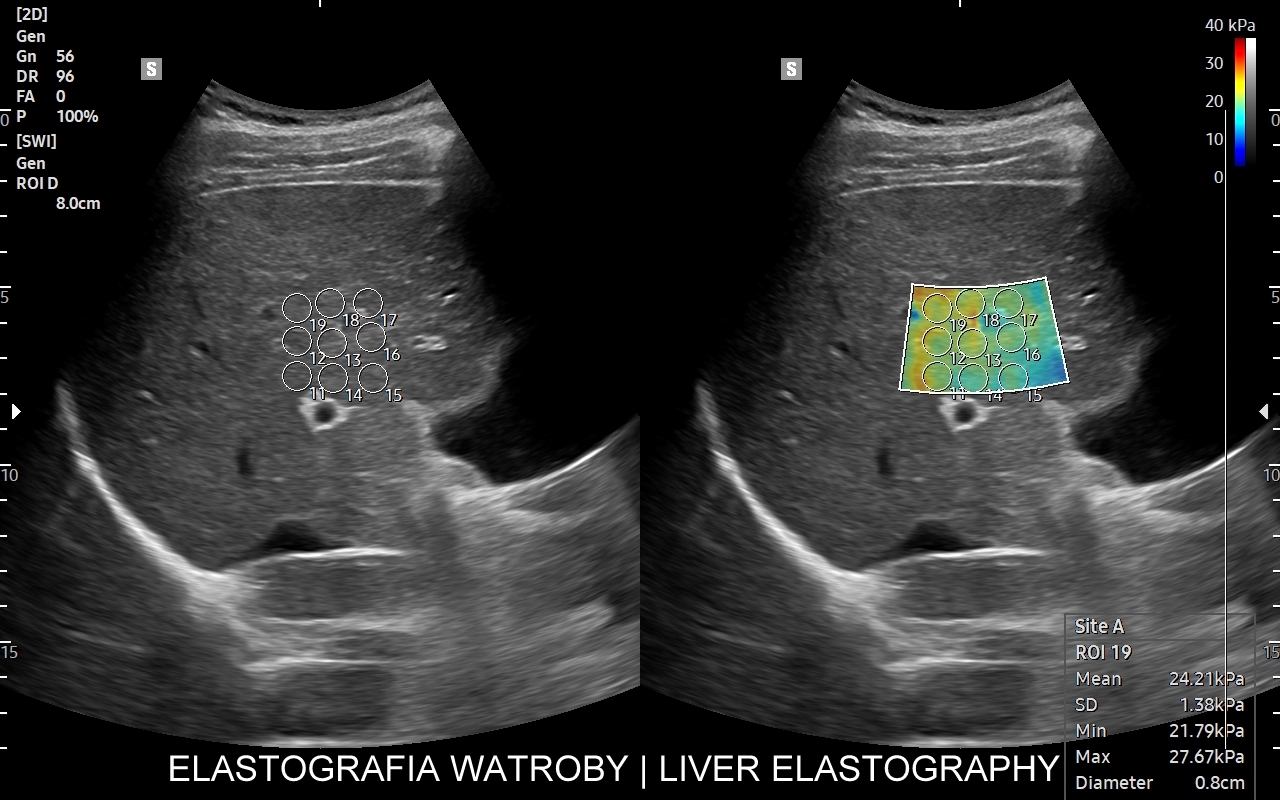

Na przestrzeni czasu metoda SWI ulegała ewolucji. Jej starsza odmiana to tzw. Fibroscan, który jest badaniem „na ślepo”, gdyż nie umożliwia precyzyjnego wyboru miejsca oceny miąższu wątroby. Odmianą najnowszą i wysoce precyzyjną jest elastografia 2D-SWE (2D sheer wave elastography). W badaniu 2D-SWE możliwy jest wybór konkretnego miejsca pomiaru w obrębie wątroby; dodatkowo generowana jest mapa kodowaną kolorem odpowiadająca mnogim punktom pomiaru, które następnie w trakcie post-processingu można wybrać w celu uzyskania dokładnego i wiarygodnego wyniku.

W jakim celu wykonywana jest elastografia wątroby? Elastografia 2D-SWE precyzyjnie ocenia sztywność miąższu wątroby, która to wzrasta w procesie włóknienia na tle przewlekłych schorzeń narządu, np. zapaleń. Badanie pozwala w ten sposób ocenić stopień zaawansowania zwłóknienia lub marskości wątroby. Dokładność oszacowania zwłóknienia w elastografii 2D-swe jest na tyle precyzyjna, iż zastępuje ona w omawianym wskazaniu medycznym biopsję wątroby.